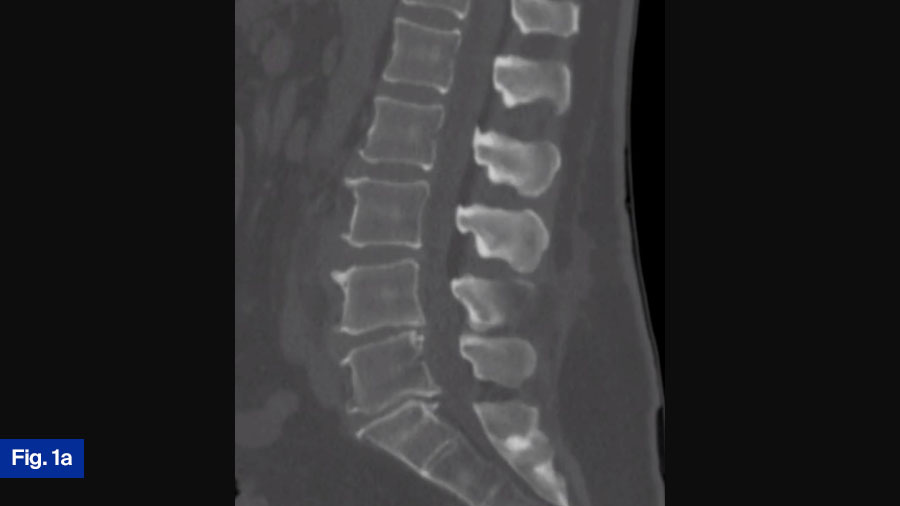

Upon presentation to the ED, he was initially treated with supportive measures/pain control for his back pain. His mention of fevers/chills prompted the ED staff to draw inflammatory labs, which were elevated. Additionally, blood cultures were draw, which eventually grew bacteroides. Due to the elevated blood cultures, and his unrelenting low back pain despite pain control efforts, advanced imaging was obtained. Noncontrasted computed tomography (CT) scan of his spine showed age-appropriate degenerative changes, but was negative for acute findings, and did not show any bony destruction (Figure 1a). A noncontrasted magnetic resonance imaging (MRI) scan of the spine was obtained, which demonstrated a small prevertebral collection without neural compression, and slight end-plate hyperintensity at the L3-L4 level. Additionally, there were L4-L5 and L5-S1 Modic changes (Figure 1b).

In summary, this neurologically intact 56-year-old man presents with a new diagnosis of discitis osteomyelitis based on the CT and MRI findings. I would most often obtain a contrast-enhanced MRI to confirm diagnosis and complete investigations. Typical surgical indications in these cases are 1) neurological deficits, 2) instability, and lastly 3) medical treatment failure. The patient is neurologically intact. The CT scan and MRI show his spine to be stable with preserved alignment and no significant bony destruction. This is a new diagnosis, and full medical management has not been attempted. Furthermore, a bacterial pathogen has been identified allowing for targeted antibiotic therapy. Given the aforementioned factors, I would treat this patient nonoperatively with a full 6 weeks of antibiotics. I would involve the infectious diseases team who would guide targeted antibiotics treatment. Inflammatory markers would then be monitored overtime to determine response to treatment. A growing body of literature suggests that early surgical intervention may lead to improve biological cure rates but given the good clinical status of this patient and the relatively benign appearance of the imaging, I would treat this patient medically.